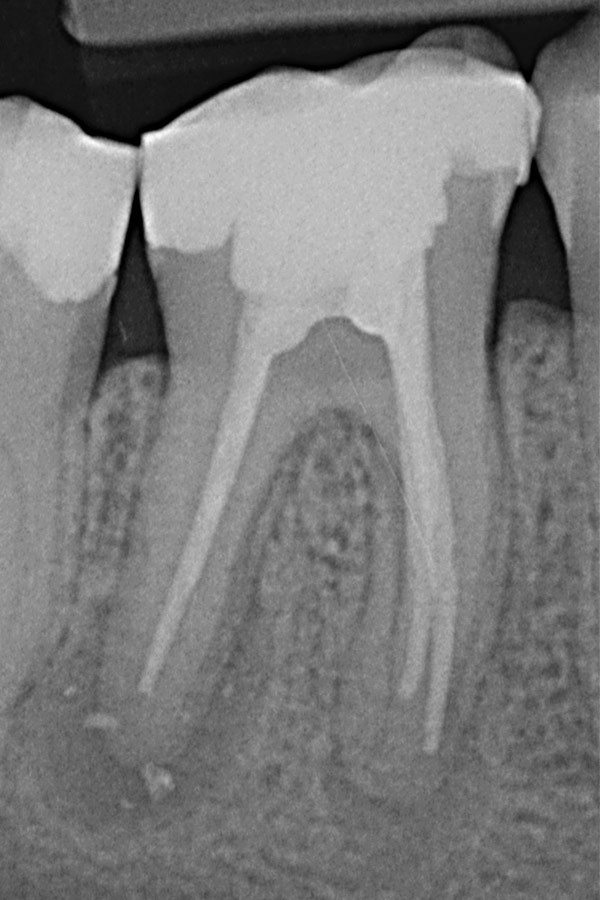

Unvollständige Wurzelfüllungen in zwei Unterkiefer-Prämolaren

Nach Revisionsbehandlung der stark verzweigten Wurzelkanäle